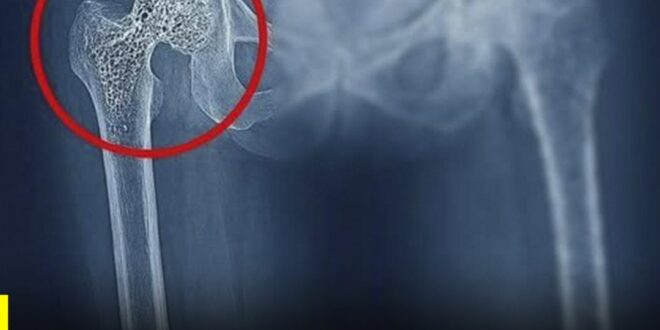

La imagen de una cadera deteriorada suele provocar una reacción inmediata incluso en quienes no tienen formación médica. Basta con ver una articulación marcada para comprender que algo importante no está funcionando como debería. Esa señal visual no representa solo una lesión puntual, sino que resume una realidad mucho más amplia: dolor persistentelimitaciones para moversetemor a realizar actividades cotidianas y, en muchos casos, un antes y un después en la vida de la persona afectada.

Entre las causas más frecuentes se encuentra la osteoporosis, una condición silenciosa que reduce la densidad de los huesos sin dar señales claras. Muchas personas descubren que la padecen recién cuando ocurre una fractura de cadera, incluso tras un movimiento leve o una caída menor. En esos casos, el diagnóstico llega tarde y el impacto físico y emocional suele ser significativo.

La imagen de una cadera dañada no es solo un estudio médico: es una advertencia. Prestar atención a las señales, consultar a tiempo y adoptar hábitos saludables puede marcar la diferencia entre una molestia controlable y un problema que transforme por completo el estilo de vida. Cuidar las caderas es, en definitiva, cuidar la libertad de movimiento y la autonomía personal.